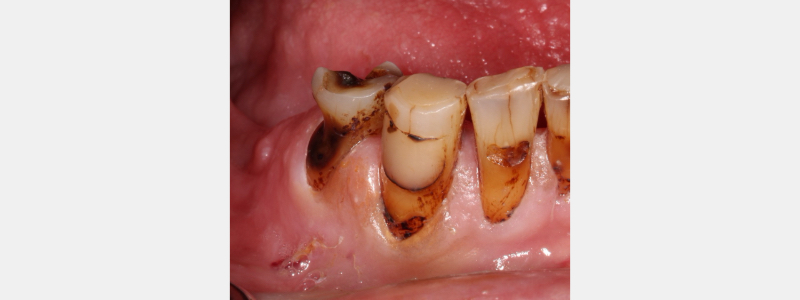

SDF can be a useful tool for conservative management of dental caries in specific clinical scenarios. Patients who have limited access to dental care, have medical or behavioral concerns that make traditional operative dentistry an extreme challenge, and have rampant dental caries can benefit from the utilization of silver diamine fluoride.

After SDF has been applied, the solution starts to kill the bacteria that have caused the carious lesion. Over a few weeks, the initial lesion will harden due to remineralization of the tooth structure.

As this occurs, the carious lesion will become darker and jet-black. The dentin in this dark, arrested carious lesion is more resistant to attack from carious bacteria than sound, unaffected dentin.

The main disadvantage of SDF is its tendency to stain active carious lesions. Healthy, unaffected enamel and dentin are resistant to staining from SDF. However dentin with carious bacteria will stain jet-black after being exposed to SDF.